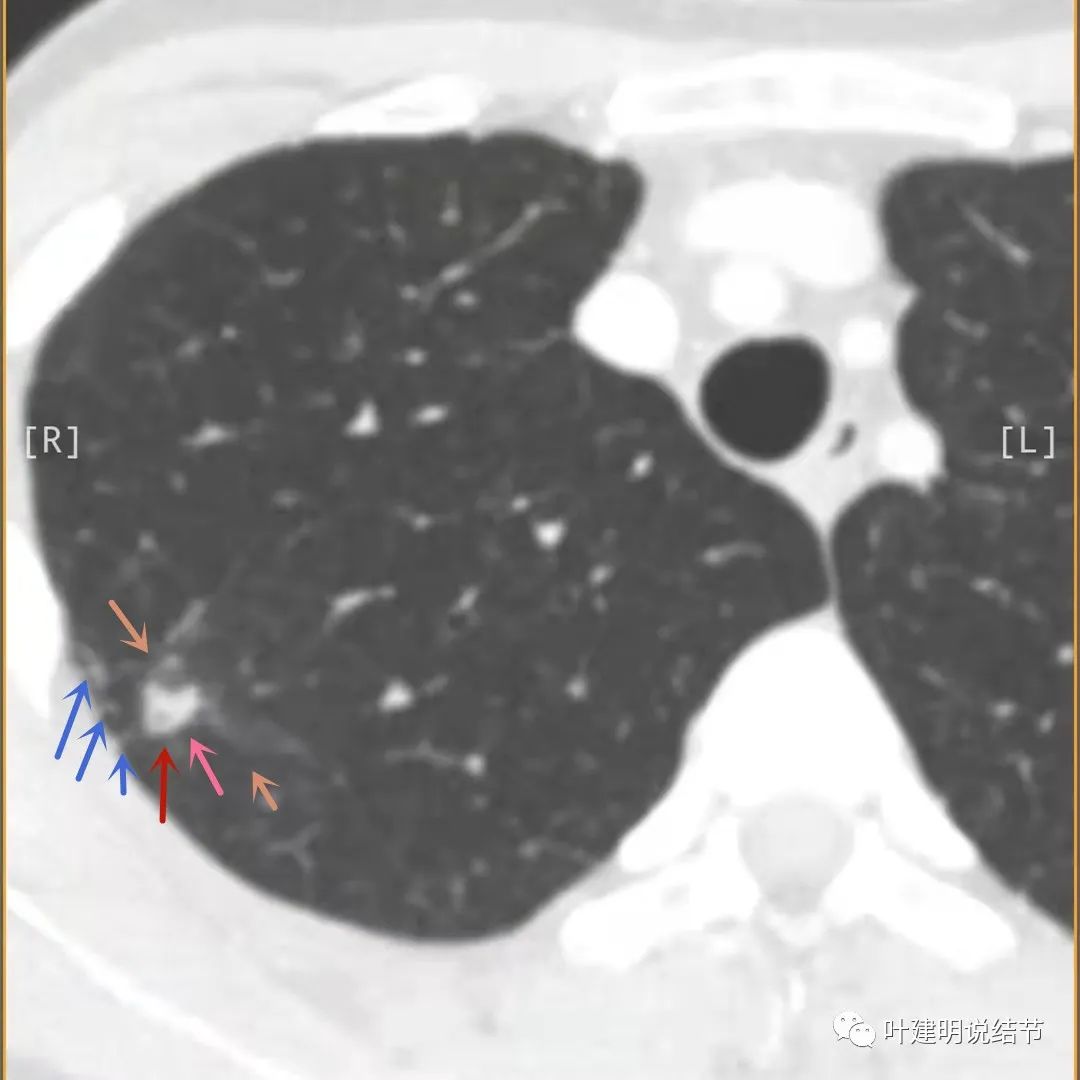

邻近胸膜有增厚(蓝色箭头),主病灶的壁密度过高且整个壁密度都高(粉色箭头),旁边有磨玻璃影,散且模糊(砖色箭头)。内壁不均质(此不舒服)

邻近胸膜有增厚(蓝色箭头),主病灶囊壁密度过高(粉色箭头),内部有突起(细红色箭头),旁边有磨玻璃影,散且模糊(砖色箭头),中间有空腔,内壁有些区域又是光滑的

邻近有卫星灶(绿色箭头),主病灶密度过高(粉色箭头),旁边有磨玻璃影,散且模糊(砖色箭头)

邻近胸膜有增厚(蓝色箭头),主病灶边缘较为平直,缺乏膨胀性(桔色箭头),实性部分密度过高(粉色箭头),旁边有磨玻璃影,散且模糊(砖色箭头)